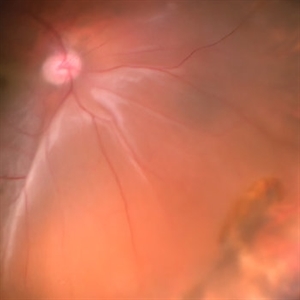

RPE rip in a case of Idiopathic polypoidal choroidopathy RPE rip in a case of Idiopathic polypoidal choroidopathyOct 23 2022 by Anjana Mirajkar, MS Ophthalmology Color photo wide field image in a of 61 year old male with RPE rip in a case of Idiopathic Polypoidal Choroidopathy. Photographer: Dr. Anjana Mirajkar -Retina Foundation, Ahmedabad Condition/keywords: RPE Rip